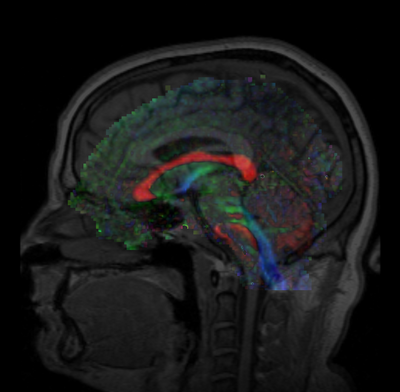

Develop a quick (< 10 min.) affine-based registration between multi-modality images for use in the AMIGO surgery suite. This module supports a fast registration using a small number of fiducials (3-5) and results in an accurately registered moving image. During this project week, we will refine the GUI and if necessary, complete work on the fiducial registration module in Slicer4.

Unregistered.png Fiducials-pre-registered.png FiducialsRegistrationResult.png